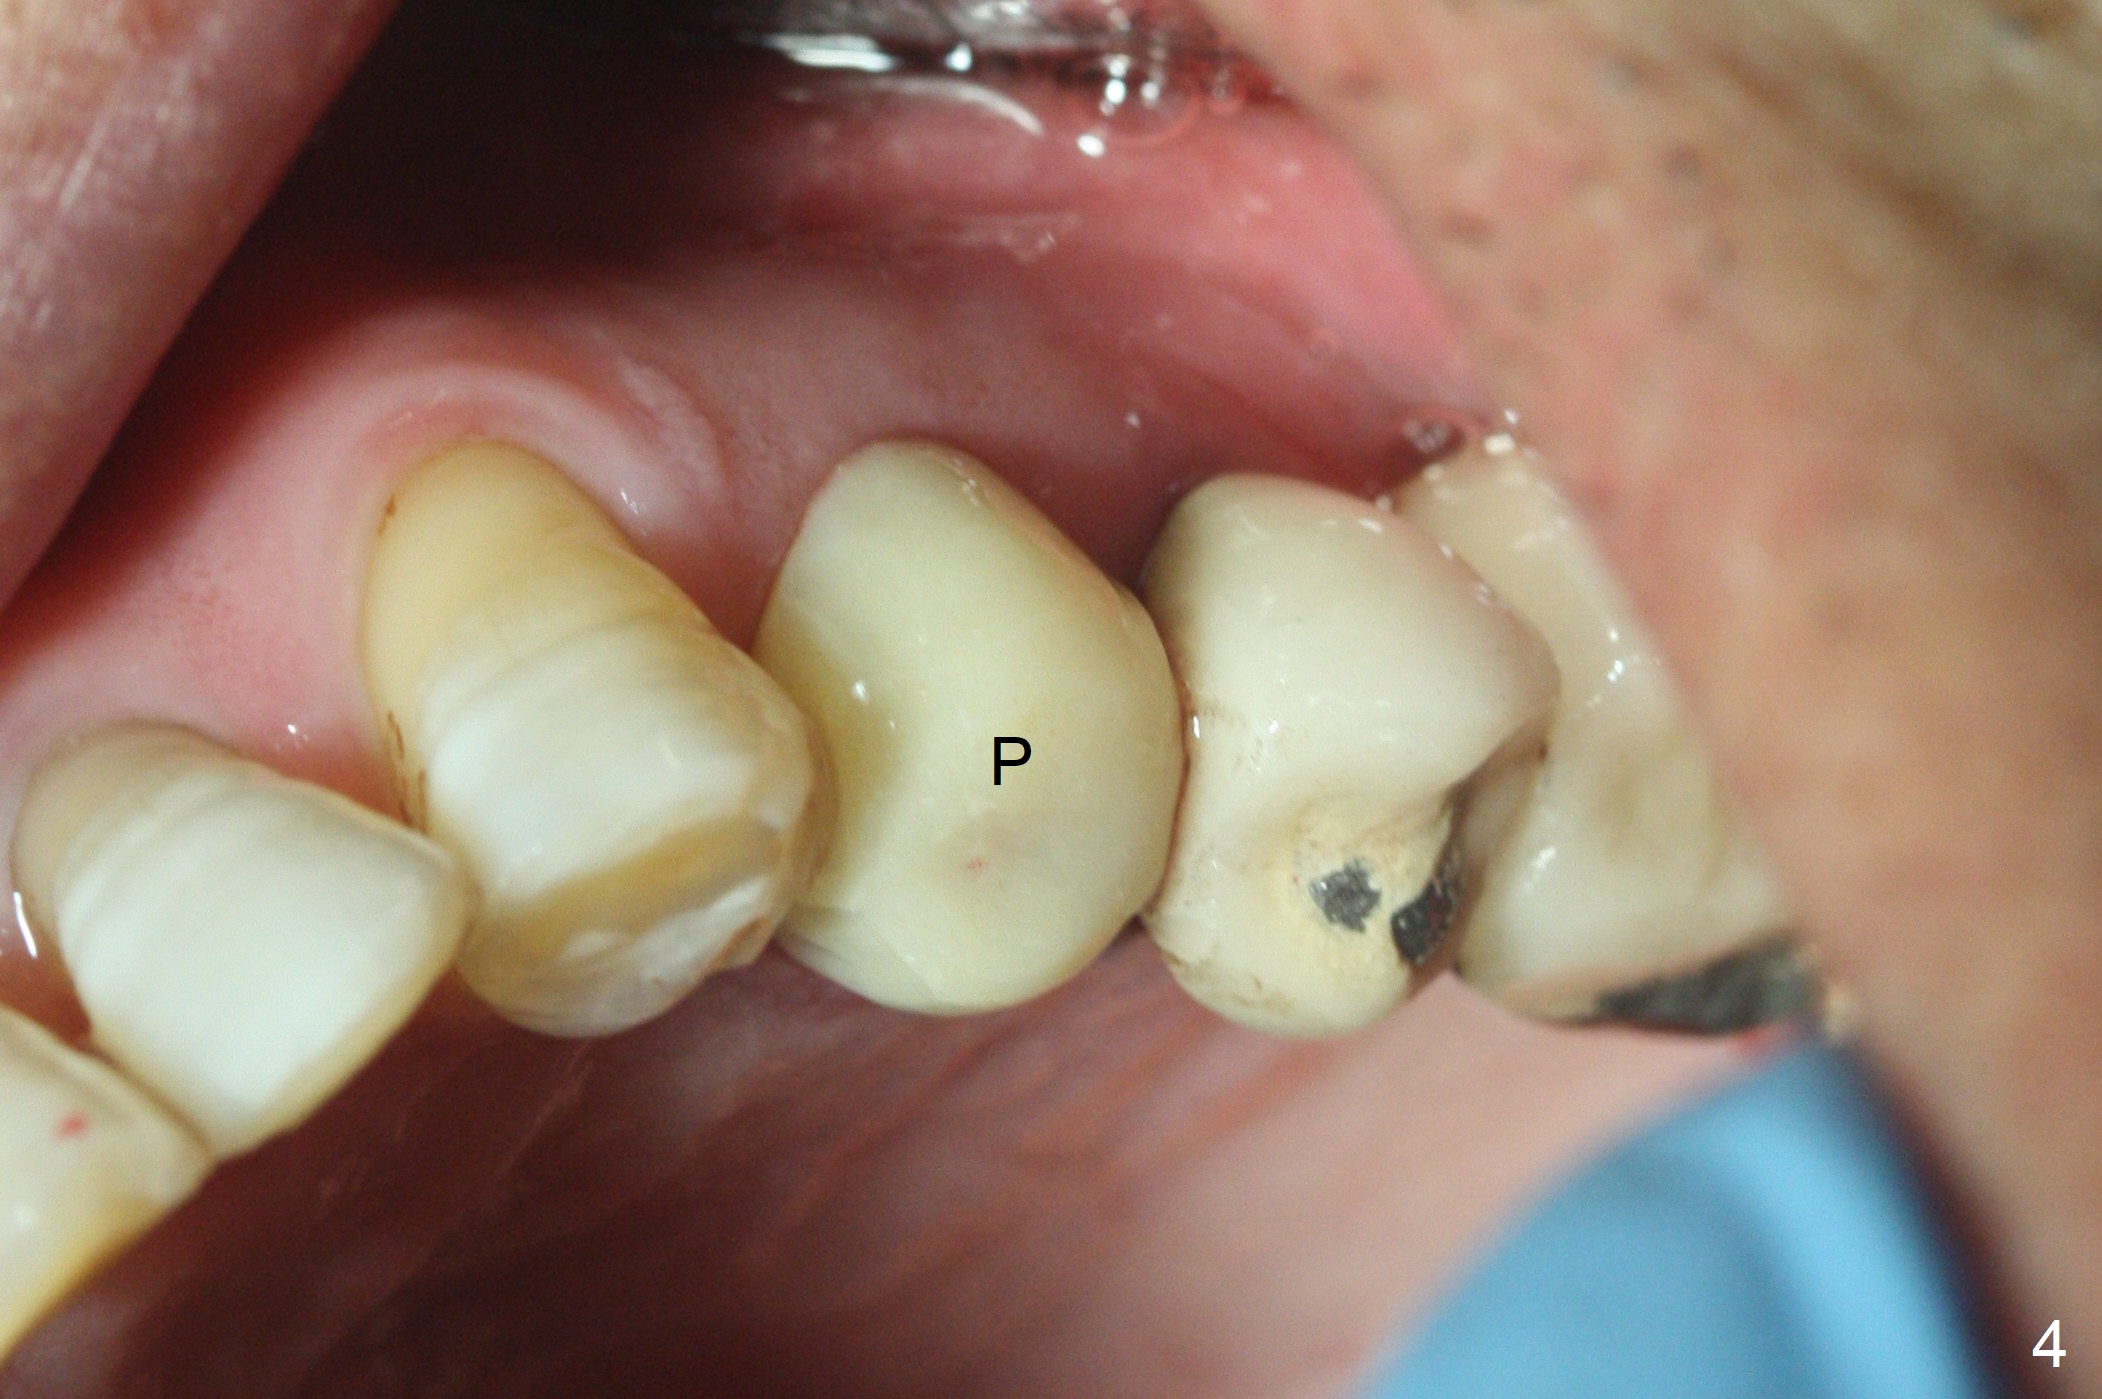

RPD Clearance